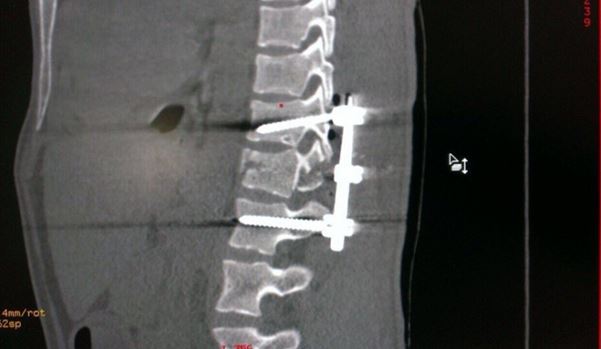

Показания для хирургического вмешательства прописываются врачами индивидуально. Основная функция операций: защита спинного мозга, стабилизация и укрепление пострадавшего сегмента позвоночника. После операции пациенты проходят курс реабилитационо-восстановительного лечения в сочетании с физиотерапевтическим и медикаментозным.

Суть операции - специалист выполняет действия, позволяющие освободить элементы нервной системы от сдавливающих костно-связочных образований от костных фрагментов и выполнить фиксацию, «разгрузку» поврежденного сегмента позвоночника с целью сращения перелома. В ряде случаев, особенно когда речь идет о «взрывном» переломе, применяется этапное лечение, суть которого заключается в замещении неопороспособного тела позвонка или тел на специализированный протез тела позвонка.

Возможно проведение малотравматичной операции через небольшие разрезы на коже. Врач по специальному проводнику под постоянной электронно-оптической навигацией осуществляет фиксацию того или иного поврежденного сегмента позвоночника, что позволяет в кратчайшие сроки пациенту подняться на ноги. При этом минимизировано возникновение осложнений, связанных с постельным режимом.